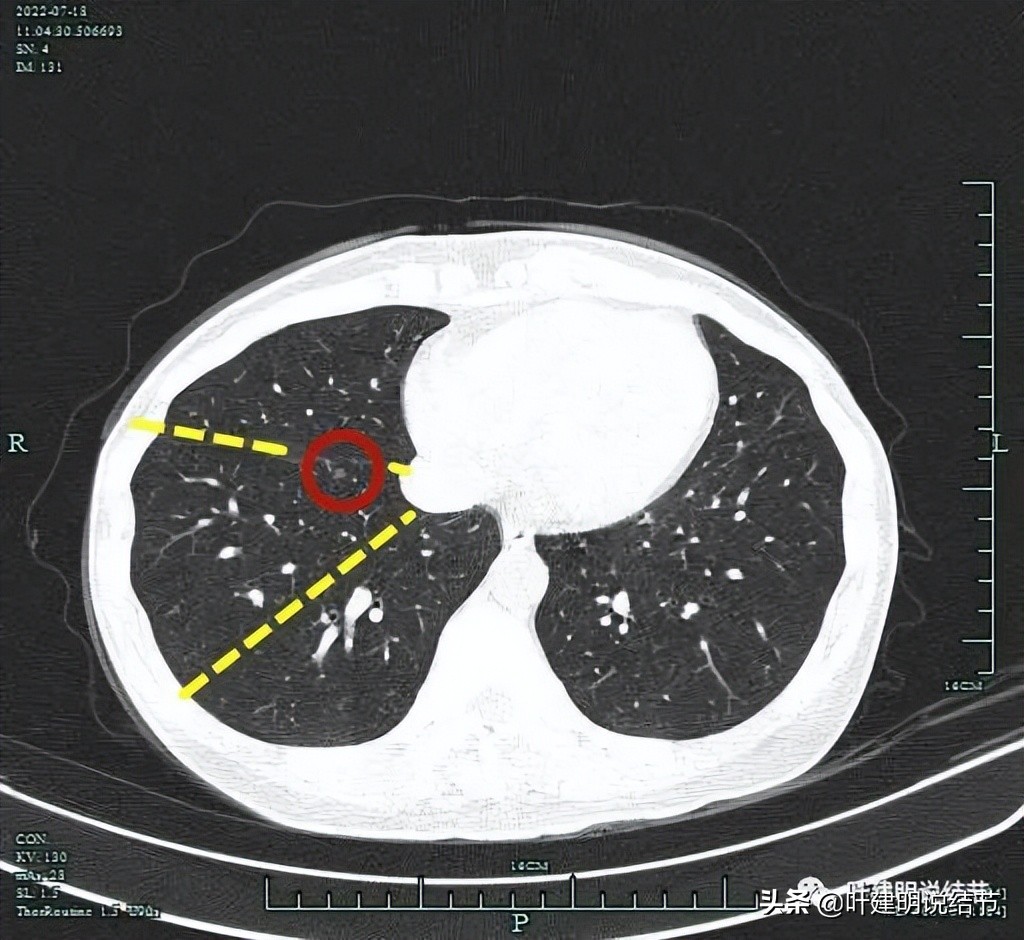

右上病灶虽然小,但密度感觉并不低,部分已经偏实性了,而且中间有小空泡征,应该要考虑恶性范围的,我判断大概率会已经是微浸润性腺癌了,至少是原位癌,但原位癌密度一般较这个要低一点。关键是位置确实挺尴尬,在右上叶邻近水平裂,与中叶交界的地方,距离肺门部大概仅约2厘米许,而且是在上叶凹进去的这个平面上,楔形切除的话,一是切割缝合器很难放到结节深面去,二是离肺门部血管近,又没有弧形的切割缝合器,容易伤到肺门部血管,许多医生可能会选择肺段切除以保证病灶能完整切除又不伤及肺门部结构。下面粉色虚线示结节到肺门血管的距离:

上图蓝色箭头示叶裂、红色示病灶轮廓与瘤肺边界清、黄色示中间有小空泡征,粉色箭头示结节与肺门部的距离仅不足2厘米,很难放置切割缝合器。